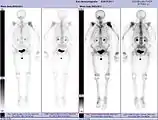

La scintigraphie osseuse est actuellement encore le meilleur moyen de diagnostic des métastases osseuses. Ce procédé est relativement sophistiqué, coûteux et soumis à quelques limites diagnostiques[90]. Contrairement à la radio, on peut avec la scintigraphie représenter assez simplement l'ensemble des attaques du squelette[87]. Une scintigraphie osseuse est normalement bien plus sensible pour la détection des métastases osseuses qu'une radio. La sensibilité de la scintigraphie osseuse est assez élevée, avec 95 %. En moyenne, avec cette méthode, les métastases osseuses sont détectées six mois avant leur mise en évidence sur la radio[113]. Par contre la spécificité est substantiellement plus faible[114], car presque toutes les modifications tumorales ou inflammatoires du squelette conduisent à un enrichissement en radiotraceurs dans le voisinage. Le remodelage plus élevé et les processus de réparation dans la bordure des métastases osseuses ostéolytiques conduisent à une accumulation plus élevée du radiotraceur, visible comme un « point chaud » sur l'image de scintigraphie[115]. Un phénomène observable de rebond (flare up) peut être dû à l’augmentation de l’activité ostéoblastique au niveau des zones d’ostéolyse tumorale clinique, dont la colonisation métastatique a été éradiquée par le traitement ; il ne doit pas être confondu avec une progression métastatique, au risque de modifier le traitement de façon intempestive[116]. Dans les métastases osseuses de cancer du poumon ou du sein, la néoformation réactive d'os peut dans de rares cas être absente[117]. Sur la scintigraphie, ceci apparaît alors comme un « point froid », un domaine avec une absorption réduite du radiotraceur[118].

La scintigraphie osseuse est avant tout utilisée pour le contrôle de la thérapie, que ce soit une chimiothérapie, une radiothérapie externe ou métabolique, pour la détermination des stades, notamment pour les cancers avec tumeur primitive inconnue, et pour le suivi après cancer[87].

Les métastases osseuses de divers cancers peuvent être très bien visualisées par TEP/scanner. Le procédé est plus sensible que la TEMP et notablement plus que la scintigraphie, cependant, plus sophistiquée, et donc plus onéreuse. Selon de type de tumeur primitive, on utilise divers traceurs, mais le plus souvent le Fluorodésoxyglucose (18F) et le fluorure de sodium NaF (18F), et aussi pour le cancer de la prostate la choline (18F). L'activité métabolique de la tumeur est le plus souvent bien visible avec le FDG, et la réaction de l'os à la métastase avec le NaF[124].